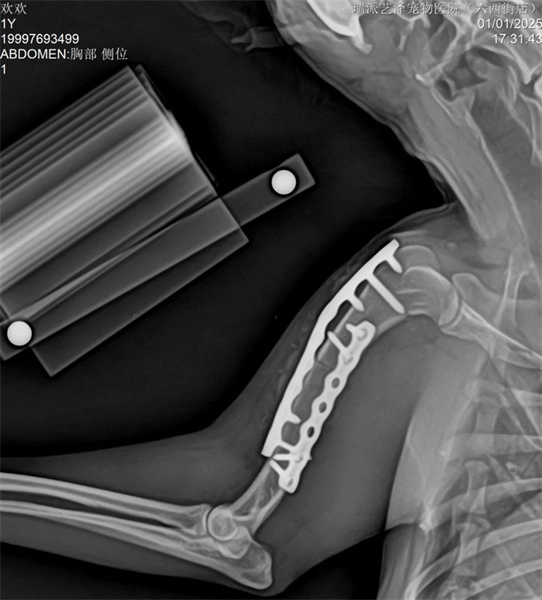

脛骨採用內側MIPO手術入路,盡可能保護軟組織,並以髓內釘及橋接骨板固定。

脛骨採用PRCL8mm接骨板和2.5mm穿刺針,確保近端和遠端至少有兩枚螺絲